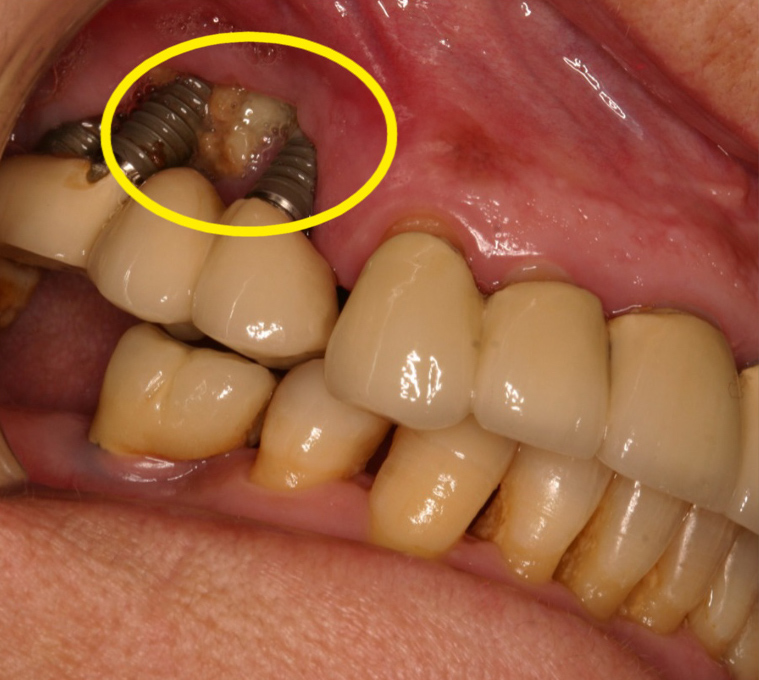

La osteonecrosis de los maxilares es una complicación poco frecuente pero importante. Se produce cuando una zona del hueso mandibular o maxilar no cicatriza correctamente y queda expuesta al medio oral durante más de ocho semanas, lo que puede causar infecciones, dolor y otras molestias.

Es un proceso en el cual una zona de la mandíbula o maxilar no consigue cicatrizar y se queda el hueso expuesto a la calidad oral, durante más de 8 semanas, causando infección y molestias

Tras cirugías orales o extracciones dentales.

Cuando existen infecciones bucales previas, como periodontitis avanzada o quistes periapicales.